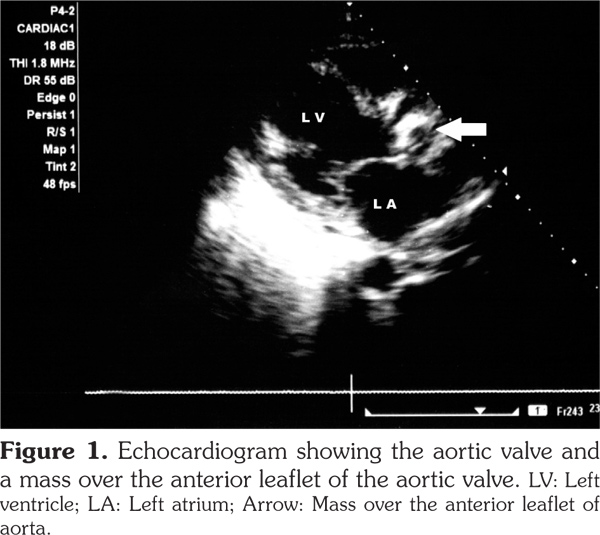

Cardiac involvement in granulomatosis with polyangiitis is rare. In this article, we describe a 47-year-old male case of aortic valve involvement with granulomatosis with polyangiitis. The patient had multi-system involvement in the form of pulmonary, renal, cutaneous involvement along with high levels of anti-proteinase 3. Echocardiography revealed a mass over the anterior leaflet of aortic valve with a mild aortic stenosis and aortic regurgitation. We suggest that clinicians should perform a thorough cardiac examination for any possible valvular involvement in patients with granulomatosis with polyangiitis.

The patient had normocytic normochromic anemia with a hemoglobin level of 8 g/dL, white blood cell count of 14000/mm3 with 80% neutrophils, serum urea value of 80 mg/dL, and serum creatinine value of 2.5 mg/dL. Serum electrolytes and liver function test results were normal. Urinalysis examination revealed protein 3+, and 15-20 red blood cells per high power field. Twenty-four-hour urine protein was 1.2 grams. Abdominal ultrasound revealed enlarged kidneys with increased echotexture and altered corticomedullary differentiation. Thoracic X-ray demonstrated bilateral pulmonary infiltrates, while computed tomography revealed bilateral patchy opacities with thickening of the right horizontal fissure and bilateral alveolar infiltrates. Echocardiography also revealed a mass over the anterior aortic valve with mild aortic stenosis and moderate aortic regurgitation (Figure 1). Anti-neutrophilic cytoplasmic antibody (ANCA) serology showed a markedly increased level of anti-proteinase 3 (anti-PR3) (31 IU/ml, cut off ≤3.5 IU/ml), and anti-myeloperoxidase (anti-MPO) level of 2.1 IU/ml (cut off ≤9 IU/ml). Blood cultures were sterile. Antinuclear antibodies, human immunodeficiency virus, hepatits B surface antigen, hepatitis C virus serologies and sputum for acid-fast bacilli were negative. A preliminary diagnosis of GPA with acute nephritis and probable alveolar hemorrhage were made based on the possibility of concomitant infective endocarditis/involvement due to GPA. The patient was firstly treated with broad-spectrum antibiotics. However, after three days of no response to the antibiotic therapy, the patient was started on pulse methylprednisolone doses of one gram per day for five days along with pulse cyclophosphamide of 750 mg, and the antibiotics were also continued. The patient improved over a period of one week, and his hemoptysis stopped. His repeat urea was 60 mg/dL, and serum creatinine level was 1.5 mg/dL. The patient was discharged with prednisolone 60 mg per day and was asked to apply to the outpatient department for the next pulse of cyclophosphamide. However, the patient did not report back and was lost to follow-up.

Our patient presented with predominantly renal and pulmonary involvement. Besides, in the course of investigation, he was found to have a valvular lesion in the form of aortic valve mass. We considered the possibility of the mass being a vasculitic lesion in view of the patient’s high disease activity in other organs including the lungs, kidneys and skin, and high titers of anti-PR3 antibodies. Additionally, no organism grew in blood cultures, and the patient responded to high doses of parenteral steroids.